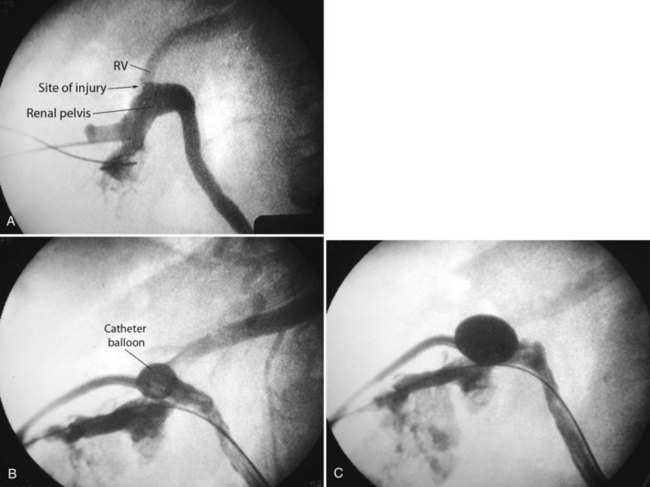

), and a guidewire can be passed from below and grasped by the nephroscope to establish through-and-through access from the external urethral meatus to the percutaneous entry site. A dual-lumen catheter can be placed as well. The small caliber of either catheter, however, does not provide much outflow from the kidney and may not prevent stone or tumor fragments from passing into the ureter along the catheter. A ureteral occlusion balloon catheter, which incorporates an approximately 15-Fr spherical balloon on the distal tip, more consistently prevents material from migrating down the ureter. The balloon should be carefully inflated in the renal pelvis, making sure the balloon is not in the ureter—which could lead to ureteral rupture—and then gently pull down to occlude the ureteropelvic junction (Fig. 47–12). Another alternative is to place a ureteral access sheath (usually 11 to 15 Fr) over a retrograde-inserted guidewire (Landman et al, 2003). The large outer diameter of the sheath effectively prevents particles from passing around the sheath into the ureter, and the large inner diameter affords excellent outflow of small stone particles. The disadvantages of employing a ureteral access sheath include the potential ureteral trauma from passing such a large device into the ureter and clogging of the catheter lumen by oversized stone fragments.

Figure 47–12 Occlusion balloon inflated and snugged down at ureteropelvic junction of contrast-filled upper tract collecting system.